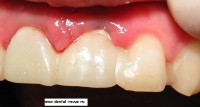

24. Временные коронки после установки.

25. Временные коронки после установки.